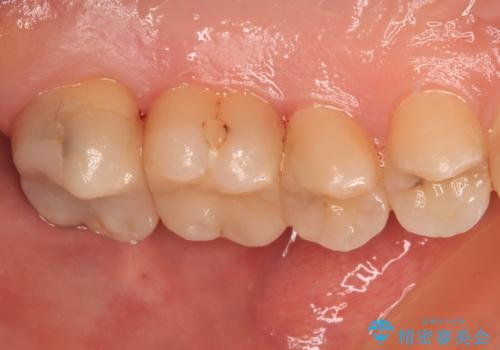

- 奥歯に頻繁に物が挟まるとのことで来院された患者様です。

最近ものが挟まりやすくなったり、冷たいものがしみるようになったりといった症状があり、診査したところ、むし歯や歯質の欠損、不適修復物などが認められました。

精度の高いセラミックインレーによる修復治療を行うこととしました。